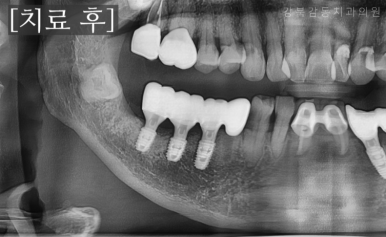

아래는 치료가 완료된 모습입니다.

뼈이식을 동반하여 새로운 임플란트 식립이 깔끔하게 잘 이루어 졌고,

수술 후 2개월 정도 회복 기간을 가진 뒤에, 보철 과정을 진행하였습니다.